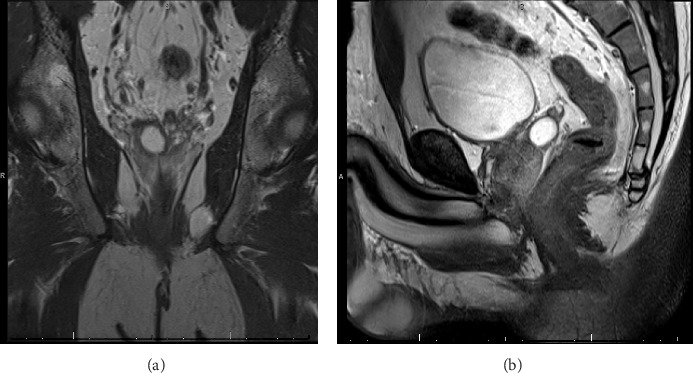

Seminal vesicle cyst (SVC) is a rare condition that can arise from congenital or acquired causes. In this report, we describe the case of a 33-year-old male who was incidentally discovered to have SVC and seminal vesicle stones following complaints of abdominal pain. He presented to the emergency department with these symptoms, which prompted further investigation and diagnosis. Computerized tomography (CT) scan revealed diverticulitis and a fluid attenuation lesion within the right aspect of the prostate gland. He was referred to urology, and further evaluation showed a right SVC of 1.8 × 1.5 × 1.5 cm on magnetic resonance imaging (MRI). The patient underwent endoscopic drainage of the SVC via transurethral seminal vesiculoscopy (TRU-SVS) and holmium laser incision. Three stones ranging from 2 to 4 mm were identified and removed with N-gage basket from the seminal vesicle resulting in successful removal of the stones and restoration of the ejaculatory duct's patency. Follow-up visits showed resolution of pain and an improvement in semen volume. This case report highlights the importance of considering SVC as a differential diagnosis in male patients presenting with such symptoms. TRU-SVS is a feasible and effective treatment option for SVC and associated seminal vesicle stones.